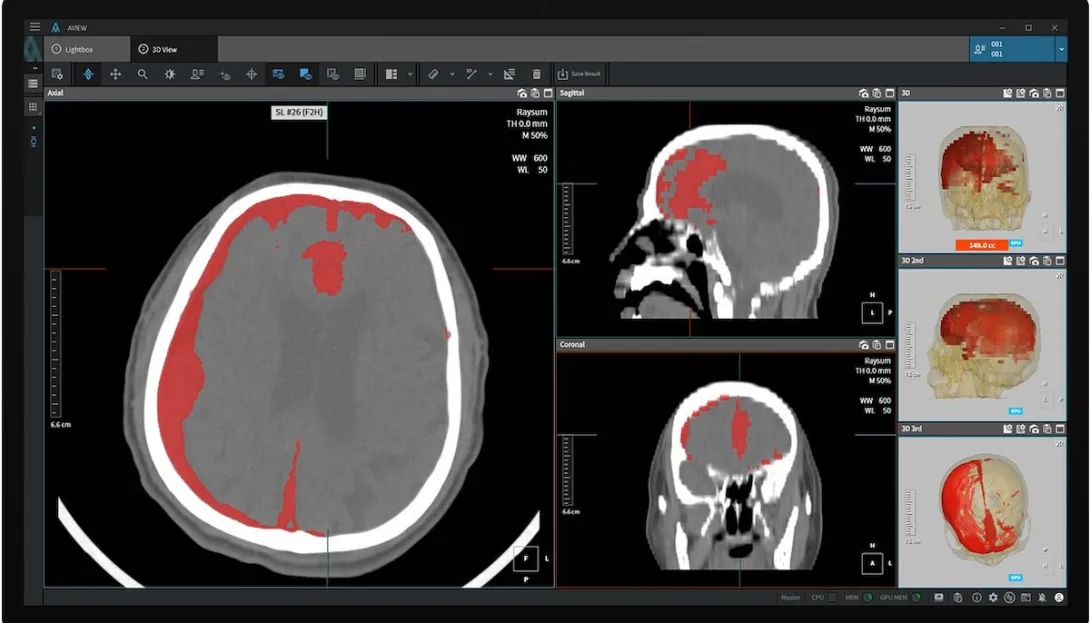

South Korea clears Coreline Soft's AI brain haemorrhage detection software

An AI-powered brain haemorrhage detection software by medtech company Coreline Soft is now listed as a non-insured medical device in South Korea following its approval from the Ministry of Food and Drug Safety.

The software product called AVIEW Neuro CAD automatically detects cerebral haemorrhages in brain CT scans and sorts them according to severity. It was recognised as an innovative medical device in South Korea last year.